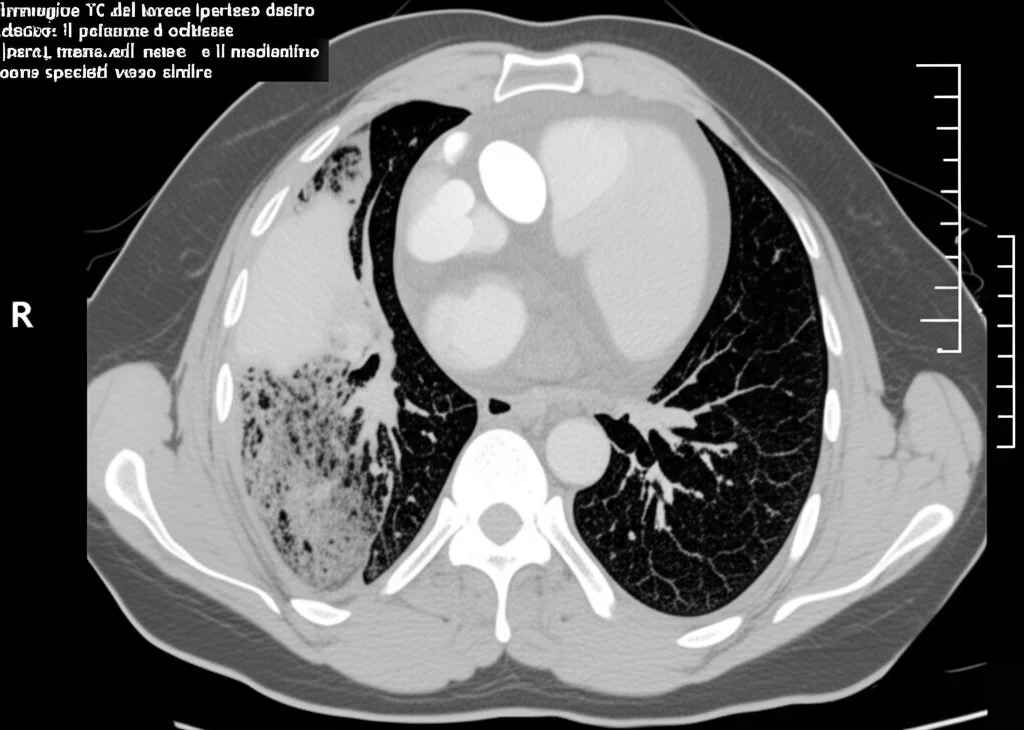

Il mattino seguente, durante il giro visite, un esame fisico più attento rivela qualcosa di strano: il torace appare gonfio, più largo del normale. Alla percussione del lato destro del torace si sente un suono timpanico, come un tamburo, e all’auscultazione non si percepisce alcun rumore respiratorio da quel lato. Il sospetto diventa quasi una certezza: pneumotorace iperteso.

Ma cos’è esattamente? Immaginate che l’aria entri nello spazio tra il polmone e la parete toracica (la cavità pleurica) e non riesca più a uscire. Si crea una sorta di valvola unidirezionale. L’aria si accumula, la pressione aumenta a dismisura, schiacciando il polmone e spostando cuore e grossi vasi sanguigni (mediastino) verso il lato opposto. Questo compromette gravemente la respirazione e la circolazione sanguigna. È una condizione gravissima che, se non trattata immediatamente, porta alla morte.

Di solito, il pneumotorace iperteso è legato a malattie polmonari preesistenti (come BPCO, tubercolosi, fibrosi polmonare) o a traumi toracici. Vederlo comparire *dopo* un’artroscopia di spalla, e per di più *due giorni dopo*, è estremamente raro. La paziente non aveva malattie polmonari note, non fumava, e la sua TAC toracica pre-operatoria era perfettamente normale.

Una TAC d’urgenza conferma la diagnosi: il polmone destro è quasi completamente collassato a causa dell’aria intrappolata.